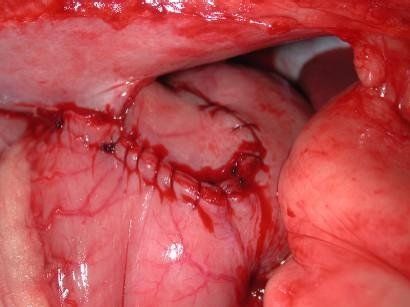

Le statistiche ci dicono che oltre 70 % dei gatti e oltre 80 % dei cani sono affetti delle patologie dentarie e gengivali già dell’età di tre anni. Medico specializzato in odontostomatologia veterinaria che dispone di attrezzatura dedicata si occupa di tutti problemi che provoca la malattia dentale:ablazione del tartaro,estrazione dei denti malati,fratturati ,denti da latte o estrazione di tutti i denti nel caso di stomatite ulcerativa nel gatto,cure endodontali.

Intervento di detartrasi si esegue in anestesia generale gassosa,soggetto è intubato e va fata continua asspirazione dei liquidi dalla bocca durante abbondante lavaggio così evitando le complicanze legate all’intervento.